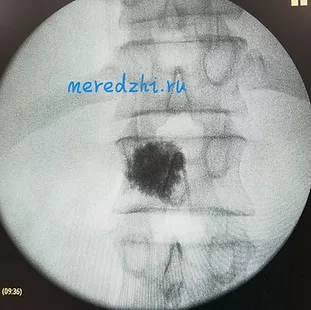

Операция осуществляется под контролем рентгеновской аппаратуры в двух проекциях, что позволяет точно определять расположение костного цемента в теле позвонка.

Рентген-контроль введения и распределение костного цемента (боковая и прямая проекции)